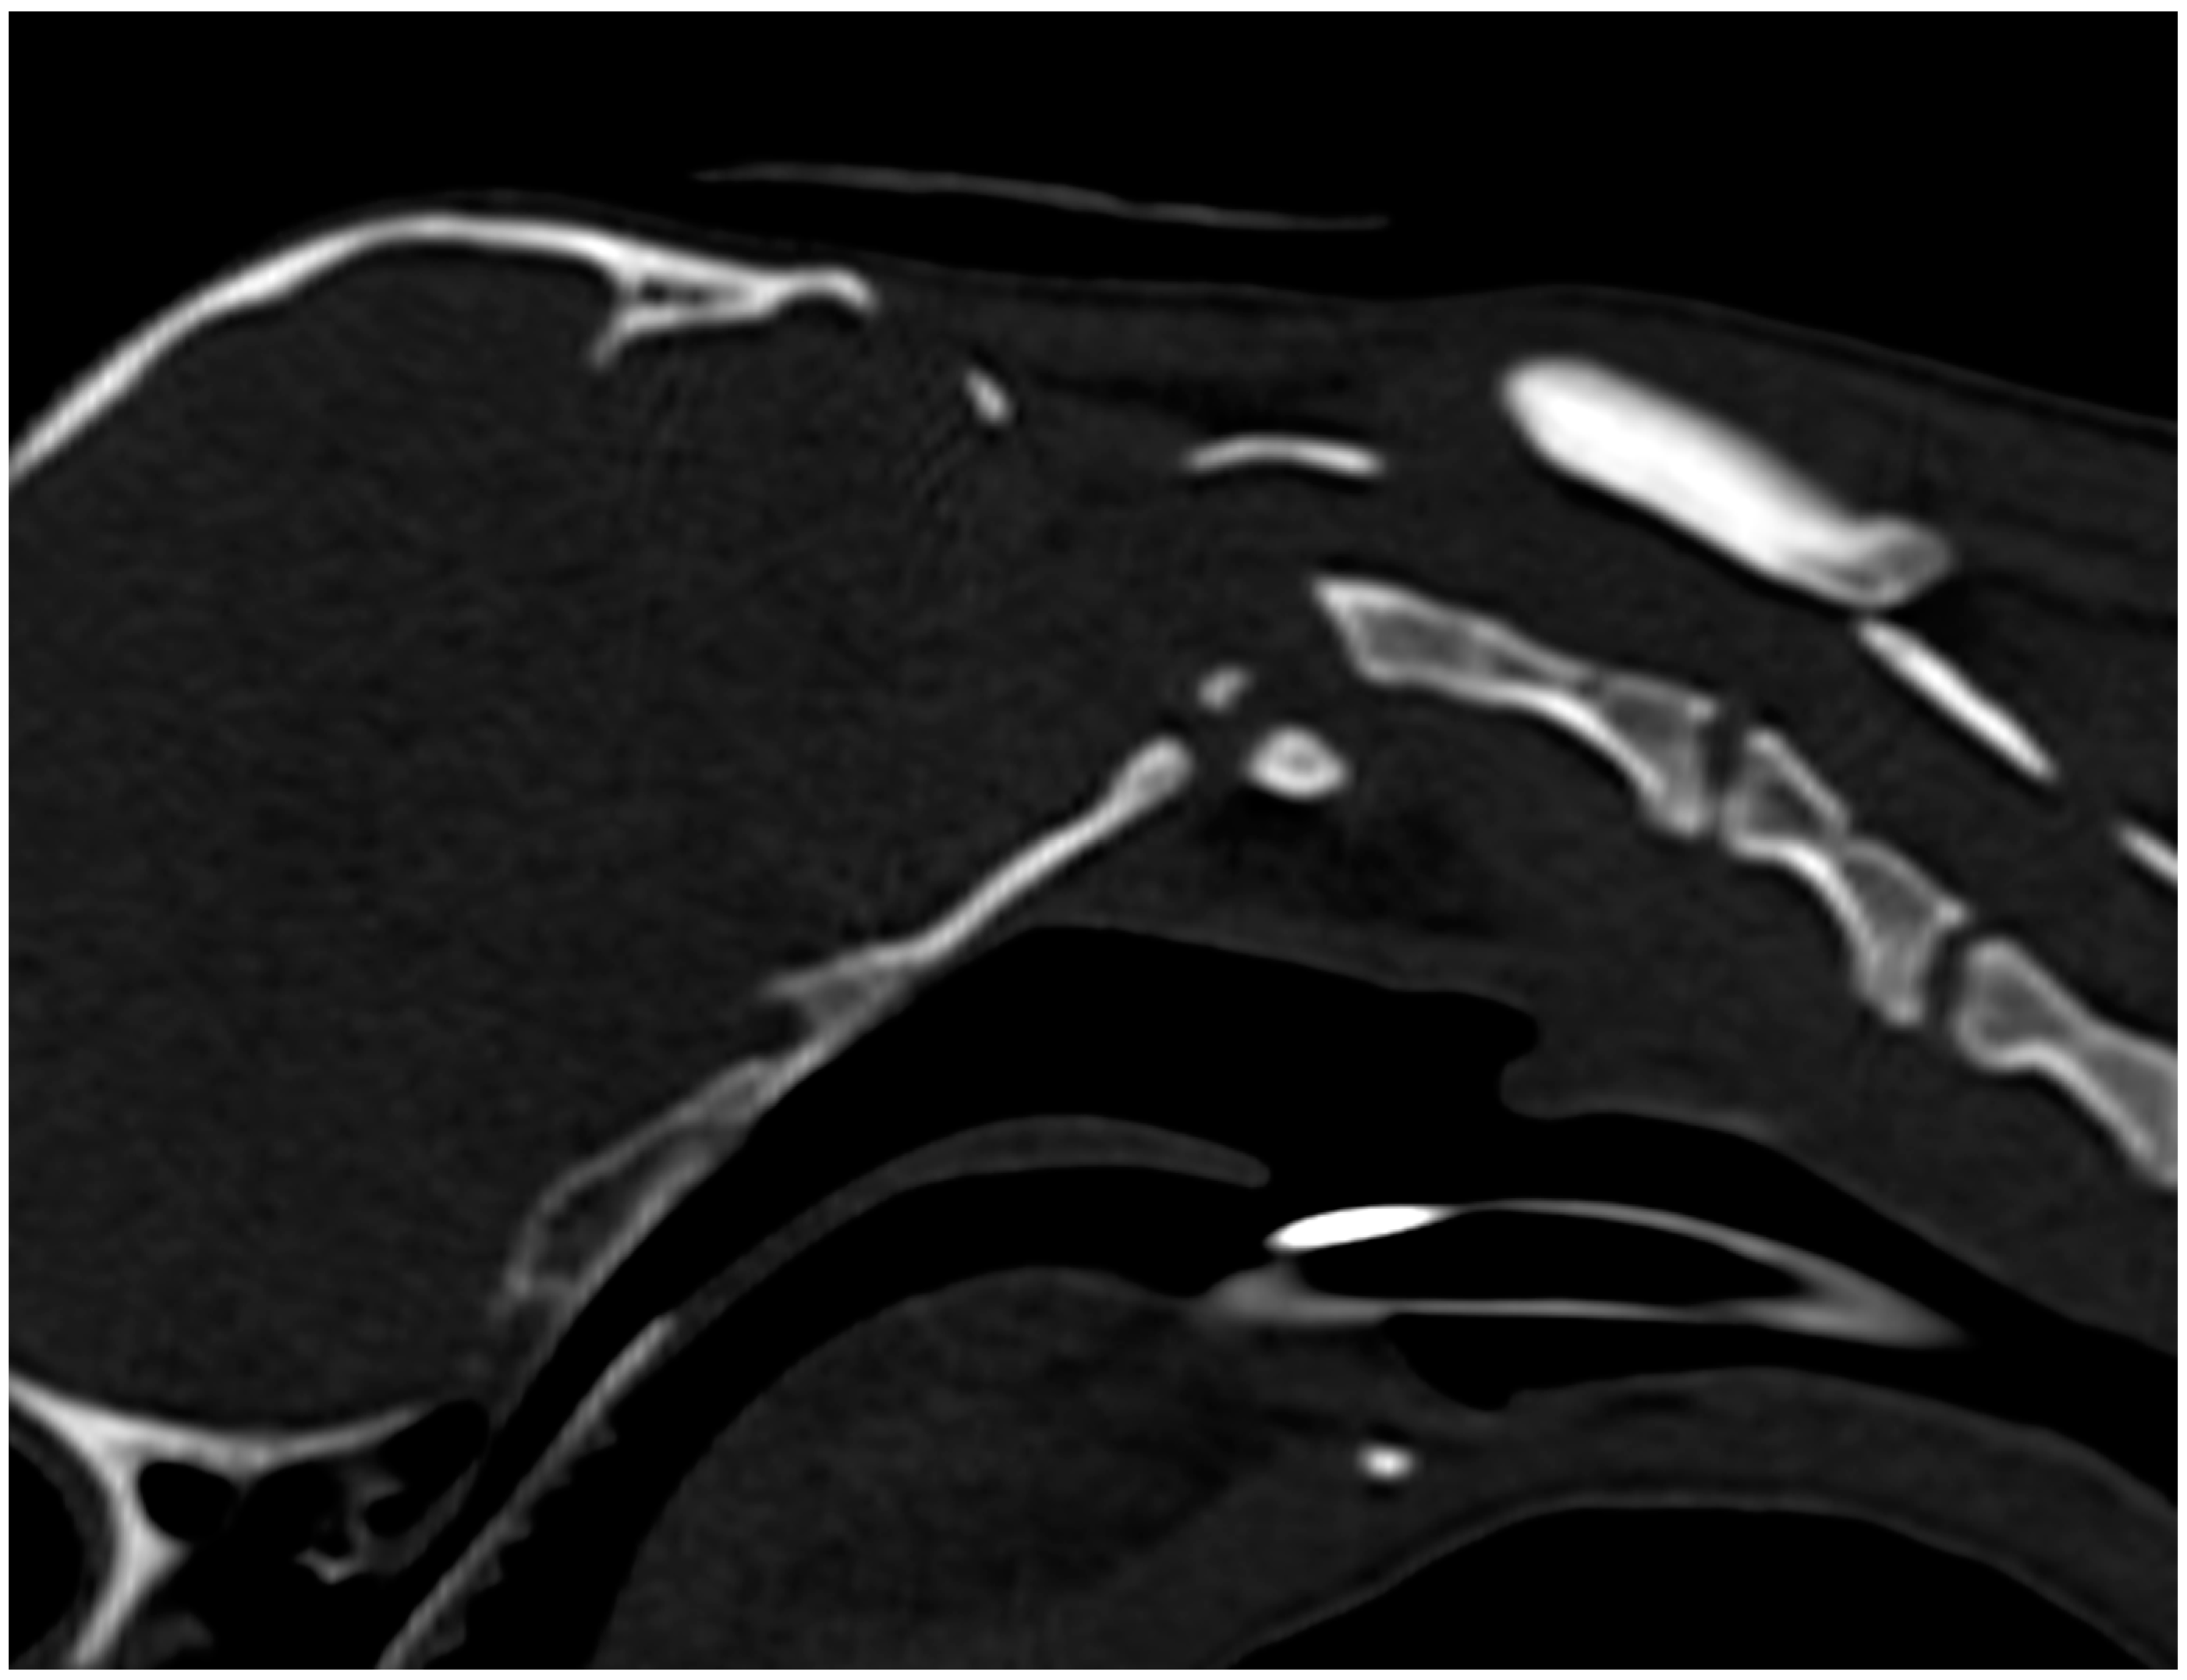

2.4.2. Computed Tomography